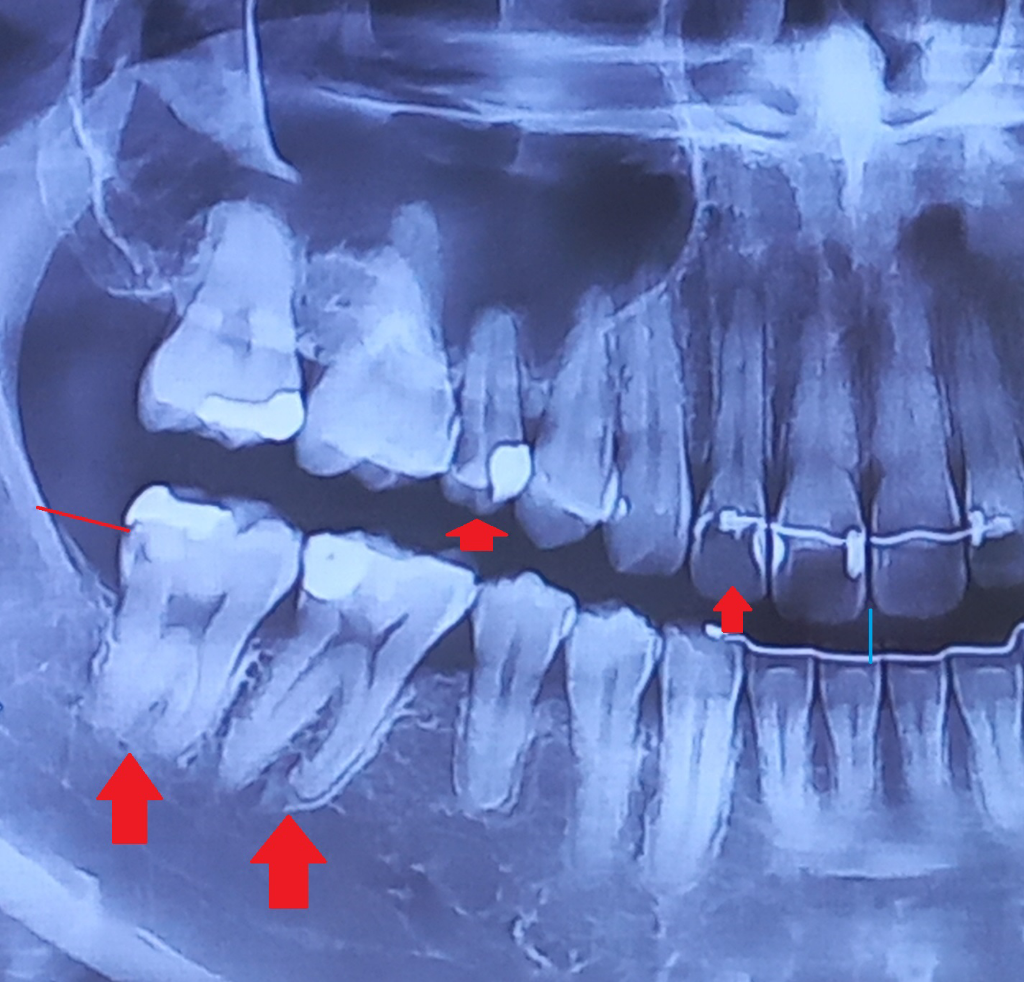

사진에서 보이는 #12 15번은 신경치료를 해야될것같습니다. #12번은 치아 뿌리끝에 염증이 잡혀 잇고 #15번은 충치가 굉장히 깊어 보입니다. #46 47은 사진상으로는 확실친 않지만 충치가 깊어 보이긴 합니다. 인레이나 크라운을 먼저 시도해보고 신경이 뚤리거나 하고나서 시리다면 신경치료를 하셔야될것같습니다 .

1. #12는 추가적으로 치근단 방사선 사진을 찍어보면 정확한 판단에 더 도움이 되겠으나 지금으로서는 치아 뿌리끝 부분 염증이 잡혀있는 상태로 신경치료가 불가피합니다.

2. #15의 경우 옆면 충치가 신경 가까이까지 깊게 들어갔기 때문에 신경치료가 들어갈 가능성을 염두해두고 옆면 인레이 충치 치료를 시도해보게 될 것 같습니다.

3. 상악동 함기화를 비롯하여, 위쪽 잇몸뼈가 굉장히 얇은 것은 맞습니다.

4. #46, 47의 경우 현재 기존 충치 수복치료한 부분 하방으로 이차 충치가 형성되었을 가능성이 보이긴 하나 이건 치근단 방사선 사진을 찍어봐야 정확합니다.